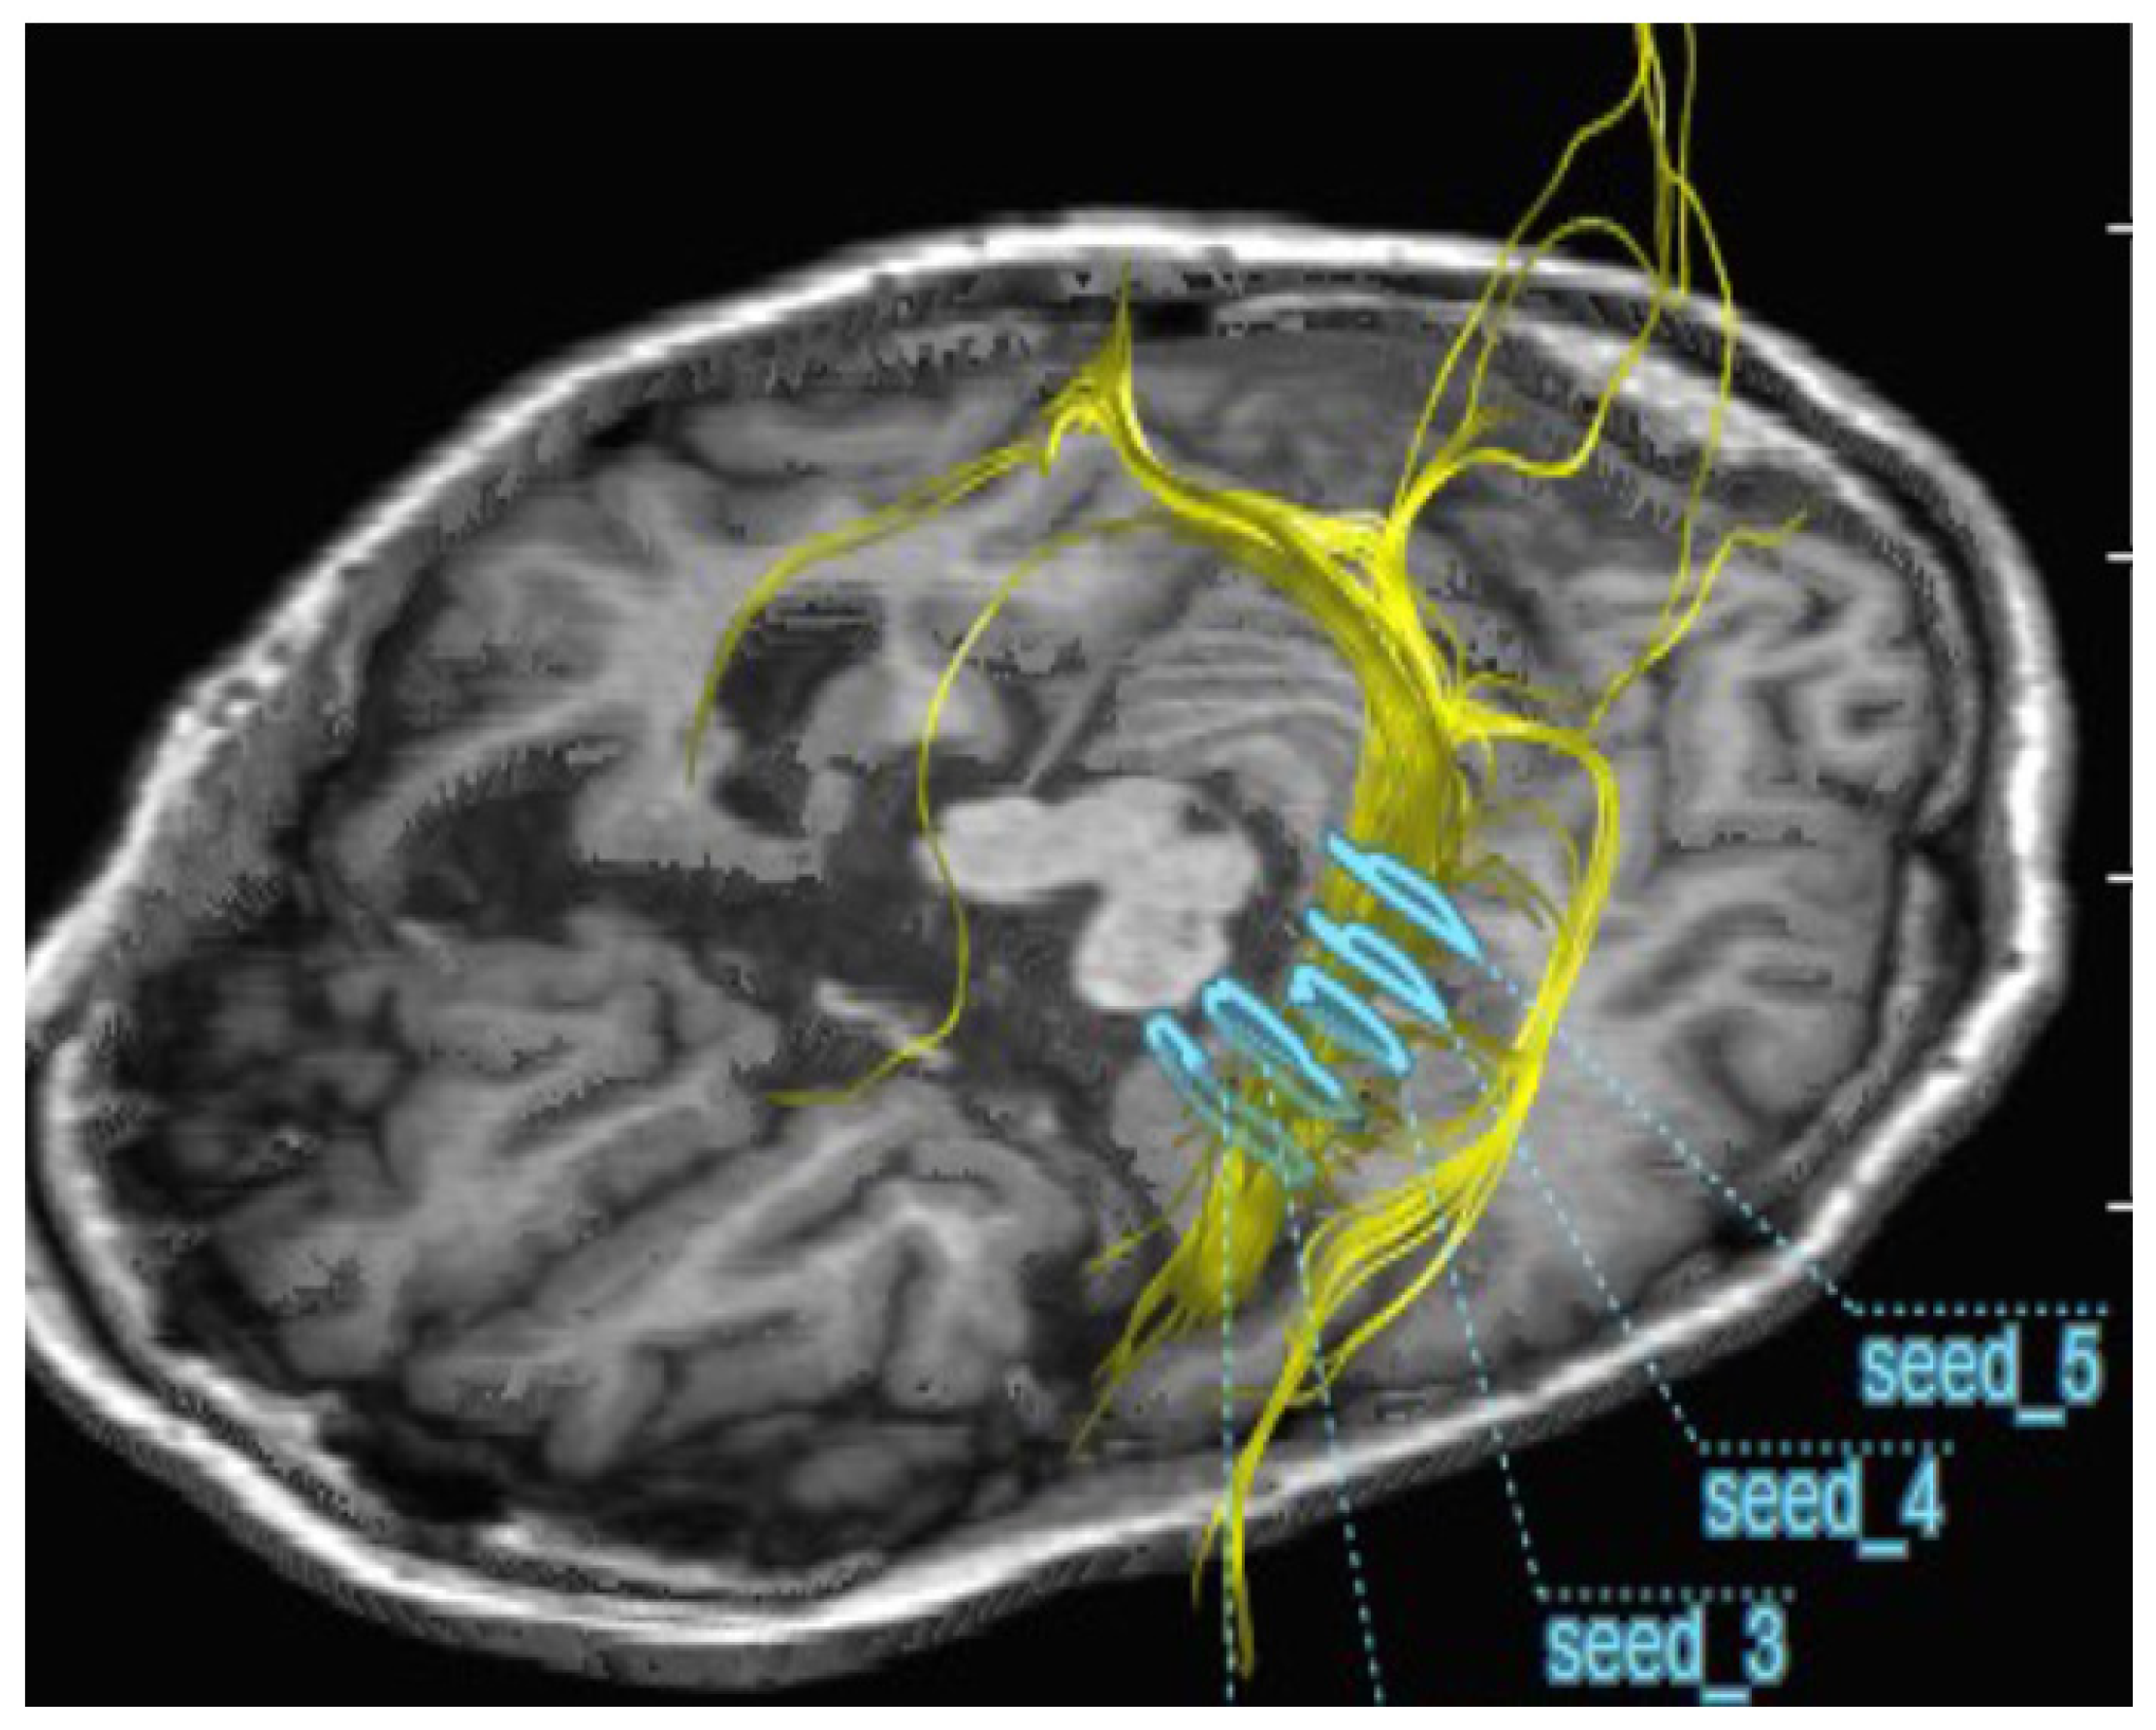

2.2. Improvement of Neurons by H2 Inhalation as Assessed by Diffusion Tensor Imaging

4.6. Measurement of the Integrity of Neurons by Diffusion Tensor Imaging